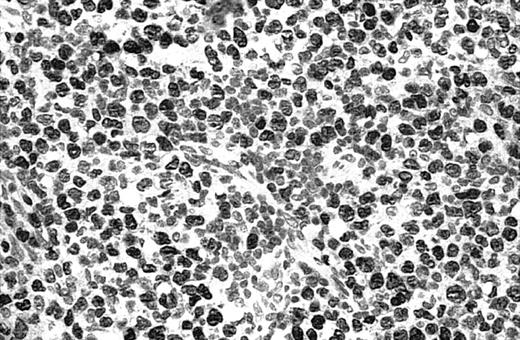

Illustration of IHC staining of JUNB in a C-ALCL patient (case 38).

This photograph (original magnification × 40) showed strong nuclear expression of JUNB by large anaplastic cells with no expression by small reactive lymphocytes.